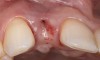

Problem: The implant is placed too facially, and there is significant labial gingival recession, contour change, and mucosal discoloration around the implant, abutment, and crown (Figure 3 and Figure 4). The implant attachment apparatus is intact and healthy, but the patient has a thin periodontal phenotype.

The following case report provides an example of this case scenario: A 28-year-old white female patient presented with her maxillary right lateral incisor significantly longer than the contralateral tooth following restoration of an existing crown that was 10 years old (Figure 3). The patient was dissatisfied with the esthetic appearance of the restoration due to the increased length, recession of the gingival tissues, and discoloration of the surrounding mucosa (Figure 4). Similar to case scenario No. 1, the first step in treatment was to decoronate the healthy implant by placing a flat surgical cover screw and employing a provisional resin-bonded-retained (RBR) prosthesis as a transitional fixed restoration (Figure 5 and Figure 6). The gingival augmentation in situ was allowed to take place for 2 to 3 weeks and was evaluated after that time (Figure 7).

Fig 3. A patient presented with a high smile line and midfacial recession of the maxillary right lateral incisor as evidenced by the increased tooth length compared with the contralateral lateral incisor.

Fig 4. Intraoral view of tooth No. 7 with the gingival zenith more apical than the adjacent central incisor and canine tooth.